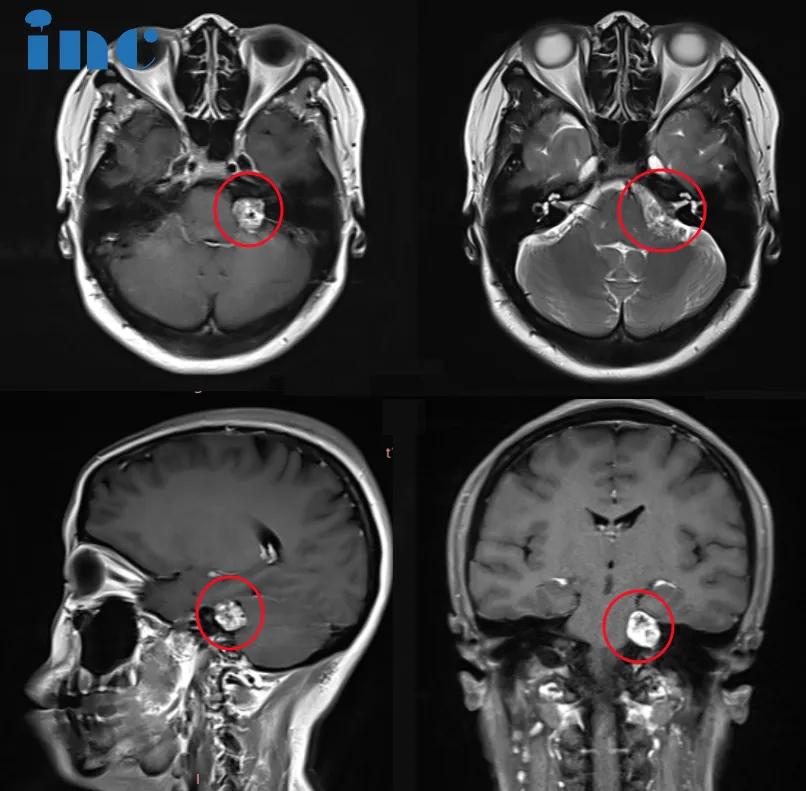

脑膜瘤属于中枢神经系统肿瘤中具有典型影像学表现的类型。在X线检查和脑室造影技术时期,检查结果仅具提示性价值。当前影像学技术可实现脑膜瘤的无创精准诊断,明确病灶与周围结构的解剖...

小脑幕脑膜瘤可起源于小脑幕任何部位,其中约50%发生在沿横窦的外侧区域,25%沿着小脑幕的内侧或游离缘分布,剩余25%主要累及小脑幕中部和同时波及小脑幕与大脑镰的肿瘤。此类肿瘤的极少部...